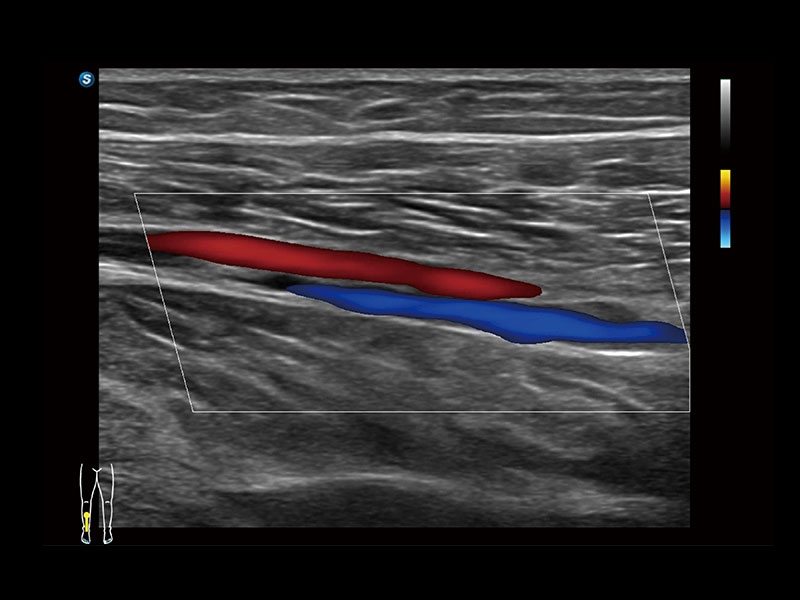

作为开立医疗全新打造的高端床旁笔记本超声,E11不仅具备卓越的图像质量,同时搭载全面高效的自动测量工具,助力医生实现更快速、更精准的床旁诊断。

E11搭载了丰富的自动化测量工具,以及专为POC科室定制的高级功能;同时配备了为急诊医师量身打造的 SonoFast急重症超声流程,以帮助临床医生最大限度的提升工作效率